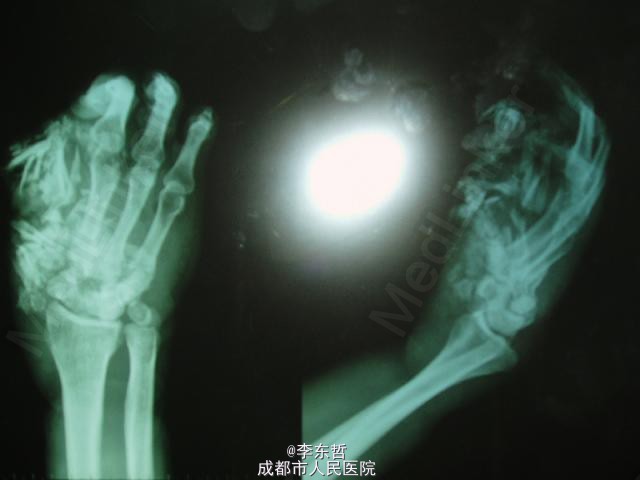

右手严重撕脱伤

李医师   成都市武侯区第一人民医院

患者中年男性,工厂上班时时被机器吞入导致严重撕脱伤,手指差不多就剩下骨头,且患有糖尿病即时血糖14mmol/L。结合本院医疗情况及患者本人、家属意见考虑截肢。